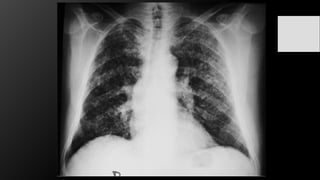

Neumonía

La neumonía en rx se manifiesta con una imagen típica de patrón alveolar y broncograma

aéreo, con distribución segmentaria, lobar o difusa, además de cambios intersticiales difusos.

-Bacteriana

-Viral

-Micótica

-Parasitaria

Patrones de la

Lobar

Segmentaria

Intersticial

Redondo

Cavitario